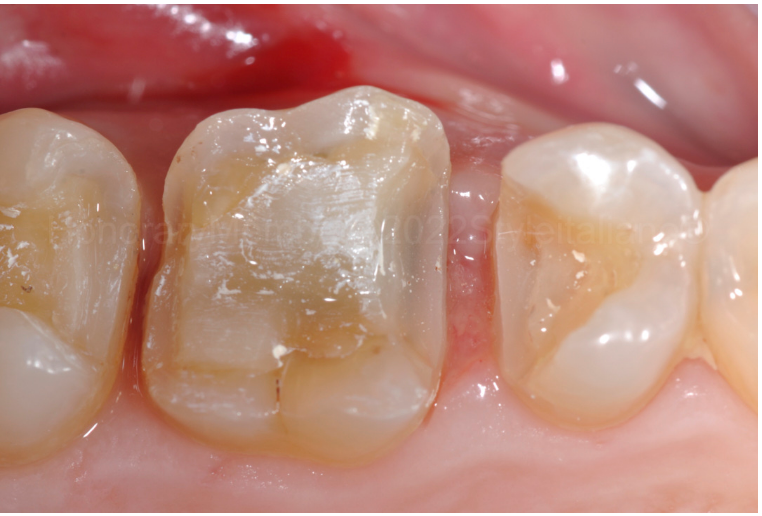

图三:即使GIC对湿性环境不敏感,为了实现深边缘的完美隔离,仍上了橡皮障和金属成型器。这一步骤至关重要,因为它是修复生物相容性的基础。一个塑料楔子被牢固地放置,使金属成型器位于龈壁下方紧贴龈壁,避免血液渗透龈壁。

图四:使用聚丙烯酸在10秒内进行表面处理。然后吹干,并进行表面干燥。